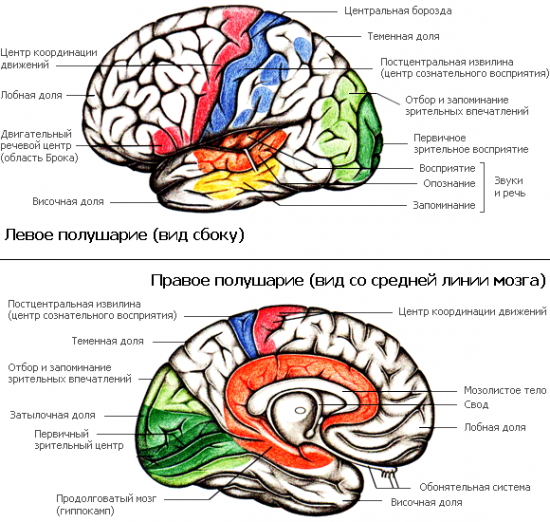

Схема чувствительных зон новой коры мозга